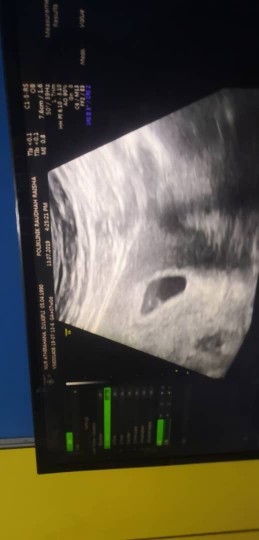

kandungan 5week

Semlm sy bru g scan.. 7w.. alhamdulillah.. da nampak heartbeat baby.. g klinik swasta

sy scan 5w nampak kantung saja.scan 8w dah nampak bby.Awal lg tu tngu 8w try g scan pulak

normal sis..sy scan masa 5weeks haritu nampak kantung je sbb bby kcik lagi dktr ckp